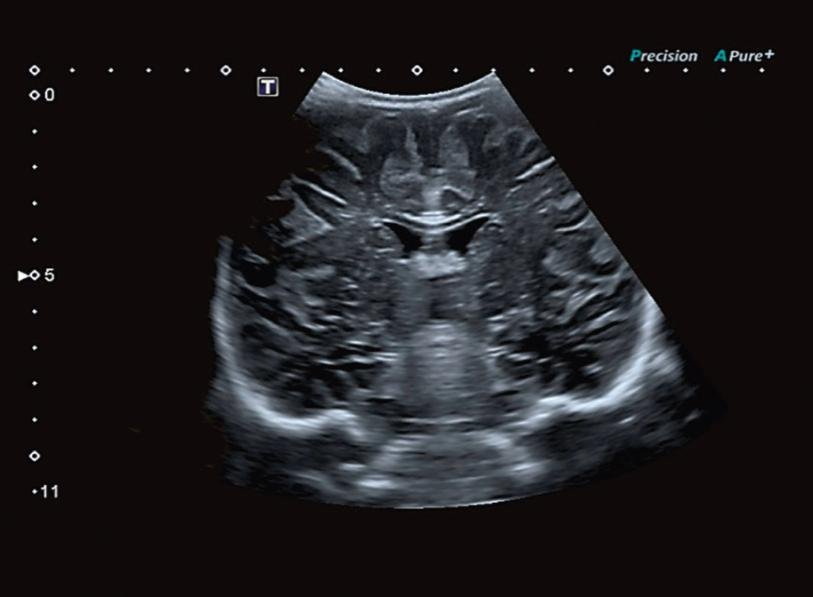

– эндокавитарным (гинекологическим).

Precision Imaging (Прецизионная визуализация) ультразвуковой системы Aplio позволяют получать более реалистичные изображения и обеспечивает высокую степень послойной дифференцировки тканевых структур и анатомическую точность в визуализации деталей.

Режим дифференцированной тканевой гармоники (DTH) обеспечивает высокую детализацию глубоко расположенных структур. Поскольку в этом режиме за один импульс передаются сигналы на двух различных частотах, изображения обладают непревзойденным пространственным разрешением и контрастностью, а также большей глубиной проникновения.